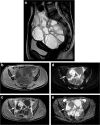

Objectives: The use of magnetic resonance (MR) imaging in differentiation between benign and malignant adnexal masses in children and adolescents might be of great value in the diagnostic workup of sonographically indeterminate masses, since preserving fertility is of particular importance in this population. This systematic review evaluates the diagnostic value of MR imaging in children with an ovarian mass.

Results: Sixteen paediatric and 18 adult studies were included. In the included studies, MR imaging has shown good diagnostic performance in differentiating between benign and malignant ovarian masses. MR imaging techniques including diffusion-weighted imaging (DWI) and dynamic contrast-enhanced (DCE) imaging seem to further improve the diagnostic performance.

Conclusion: The addition of DWI with apparent diffusion coefficient (ADC) values measured in enhancing components of solid lesions and DCE imaging may further increase the good diagnostic performance of MR imaging in the pre-operative differentiation between benign and malignant ovarian masses by increasing specificity. Prospective age-specific studies are needed to confirm the high diagnostic performance of MR imaging in children and adolescents with a sonographically indeterminate ovarian mass.

Key points: • MR imaging, based on several morphological features, is of good diagnostic performance in differentiating between benign and malignant ovarian masses. Sensitivity and specificity varied between 84.8 to 100% and 20.0 to 98.4%, respectively. • MR imaging techniques like diffusion-weighted imaging (DWI) and dynamic contrast-enhanced (DCE) imaging seem to improve the diagnostic performance. • Specific studies in children and adolescents with ovarian masses are required to confirm the suggested increased diagnostic performance of DWI and DCE in this population.